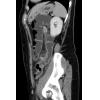

2. Welches der folgenden Organe ist auf dem sagittalen Bild nicht erfasst?

- a) Milz

- b) Leber

- c) Magen

- d) Niere

- e) Aorta

4. Welchen Befund notieren zu dem sagittalen Bild?

- a) Ausgedehnte freie intraabdominelle Luft, der ventralen Bauchwand angrenzend

- b) Ausgedehnte freie intraabdominelle Luft, besonders um die Leber

- c) Luftperlen in der Gallenblasenwand

- d) Einzelne Luftperlen ventral des Colon descendens

- e) Kein suspekter Befund, keine Luft außerhalb der Darmschlingen

5. Welche Diagnose stellen Sie?

- a) Emphysematöse Cholezystitis

- b) Perforierte Diverticulitis mit ausgedehntem Abszess

- c) Perforierte Diverticulitis mit ausgedehnter freier intraabdomineller Luft

- d) Einfache Diverticulitis ohne Perforation

- e) Gedeckt perforierte Diverticulitis